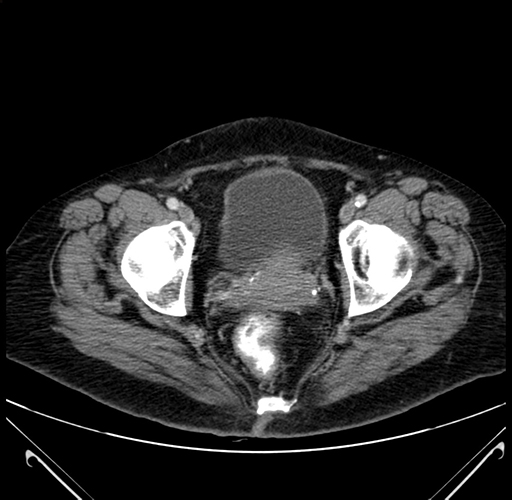

Axial Venous

Coronal Venous